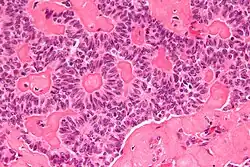

| Micrograph of a sex cord tumour with annular tubules. H&E stain. | |

Sex cord tumour with annular tubules (SCTAT) is a rare ovarian tumour in the sex cord group of gonadal tumours.

It has a distinctive appearance under the microscope, from which it derives its name.